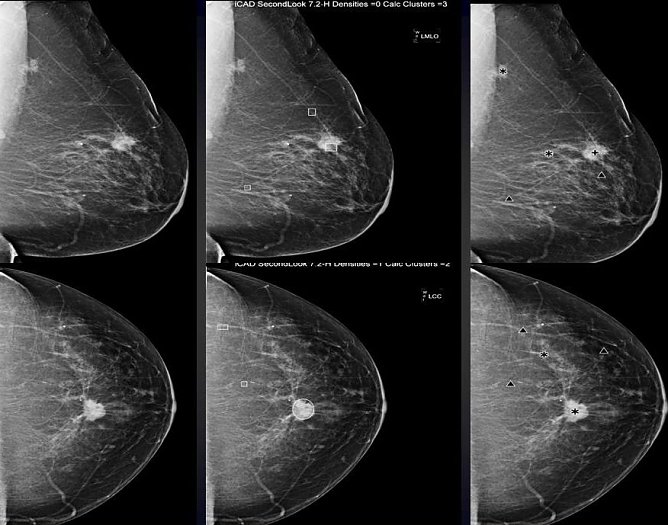

So wurden die Ergebnisse einer in Nordhausen betreuten Doktorarbeit vorgestellt. Diese Arbeit beschäftigte sich mit der computergestützten Erkennung auffälliger Strukturen in der Mammographie und analysierte hierbei vergleichend drei verschiedene derzeit in Nordhausen verfügbare Systeme. Zielstellung hierbei war, noch stärker als bislang ausschließlich auffällige Strukturen aus mammographischen Bilddaten herauszufiltern, die dann tatsächlich auch einem kleinen Karzinom oder einer Krebsvorstufe entsprechen, um so bei Patientinnen mit letztlich gutartigem Befund die bislang erforderliche klärende radiologische Brustbiopsie nicht mehr durchführen zu müssen.

Hier sieht man links eine Röntgenaufnahme der weiblichen Brust mit einem bösartigen Tumor sowie in der Mitte und rechts jeweilige computerbasierte Analysen, die mit verschiedenen Programmen (R2 und iCAD) jeweilig auffällige Strukturen in der Röntgenaufnahme (Mammographie) markieren und für den Befunder hervorheben, Verdichtungen mit Stern bzw. Kreis sowie auffälligen Mikrokalk (kann auch mit Brustkrebs assoziiert sein) mit Dreieck bzw. Viereck (je nach Hersteller der Software unterschiedlich).

Prof. Malich wurde während des Europäischen Röntgenkongresses für die Präsentation über die computerassistierten Diagnosesysteme für die beste wissenschaftliche Präsentation ausgezeichnet.